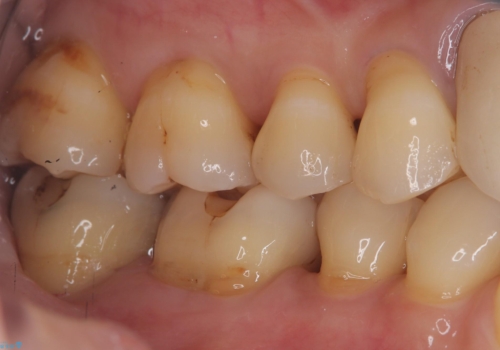

今回残存歯質量から破折のリスクを説明し、クラウンでのやり替えも提案しましたが歯質切削量が多くなることから一度インレーで様子を見ることとなりました。

セラミックインレーセット時はラバーダム防湿を行っています。